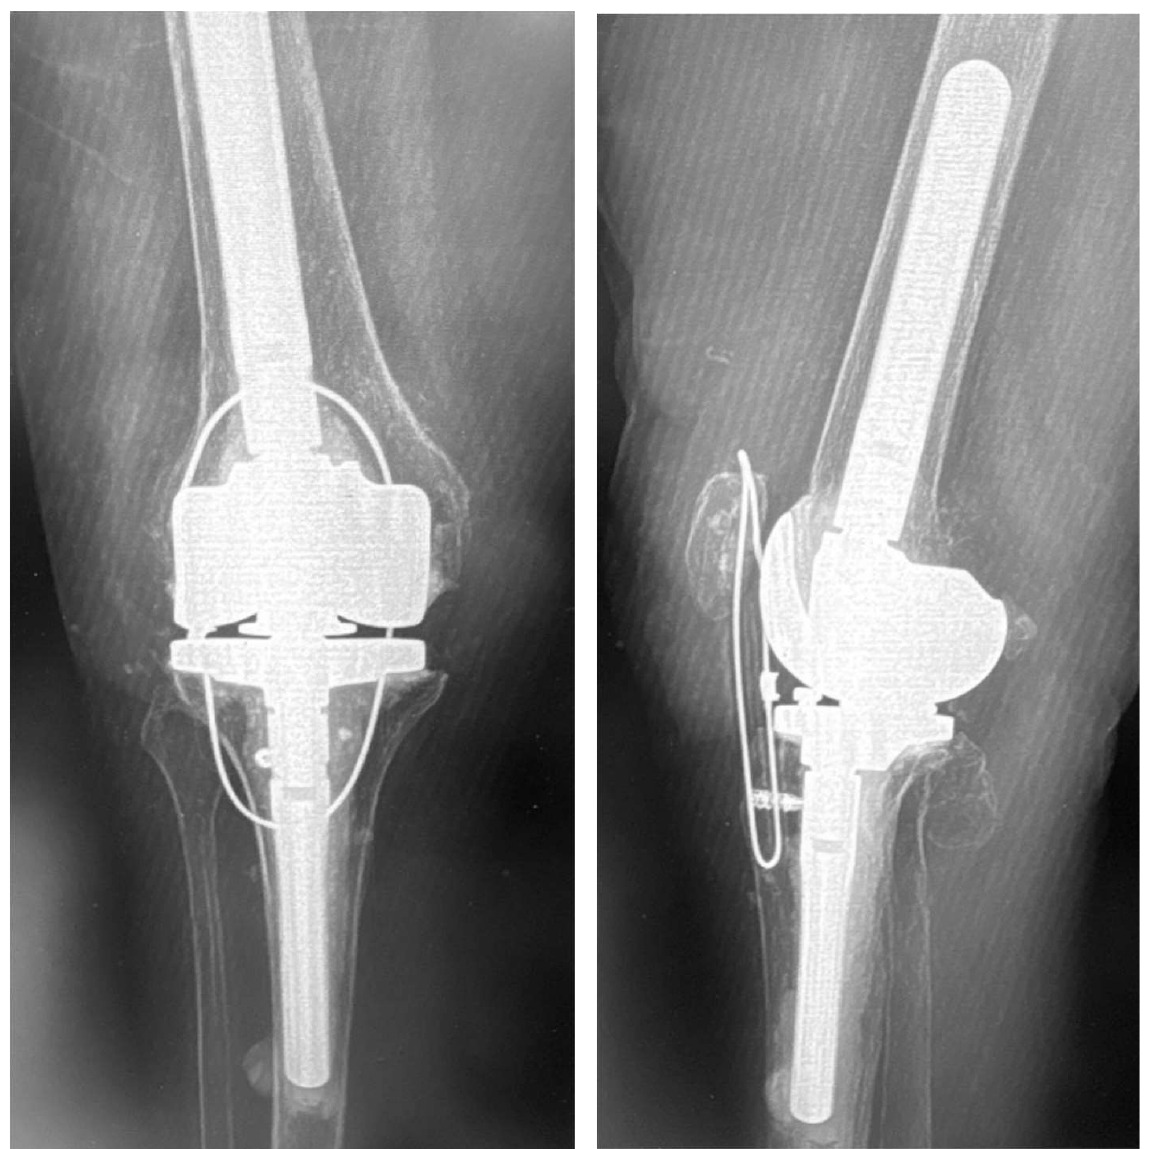

Case 2 is a 65-year-old woman with a previous oncological history and implantation with a TKA. Her knee became infected and required component removal and reimplantation with a rotating hinge. In 2013 she fell and tore patellar tendon and dislocated the patella. The patella was relocated, tear was repaired, and the protection technique used. (Figure 11A-B)

Her recovery was uneventful and was “doing great!” In 2015 (2-years following repair), she requested that the cable removed. Unfortunately, in 2016, she fell again and re-ruptured her patellar tendon. The rotating hinge was retained in place and the patellar repair / protection technique performed. She was recently seen in September of 2025 (9.5 years post second repair) and reports full independent activities of daily living (ADL) without ambulatory aids. She has a slight “lag” and weakness, so I requested that she use a cain when outside. She has ROM through 104 degrees, but that is due to the mechanical limits built into the rotating hinge device.

She did mention that she could feel the cable “a little bit.” But urprisingly, when I offered to remove it, she said to leave it as is.